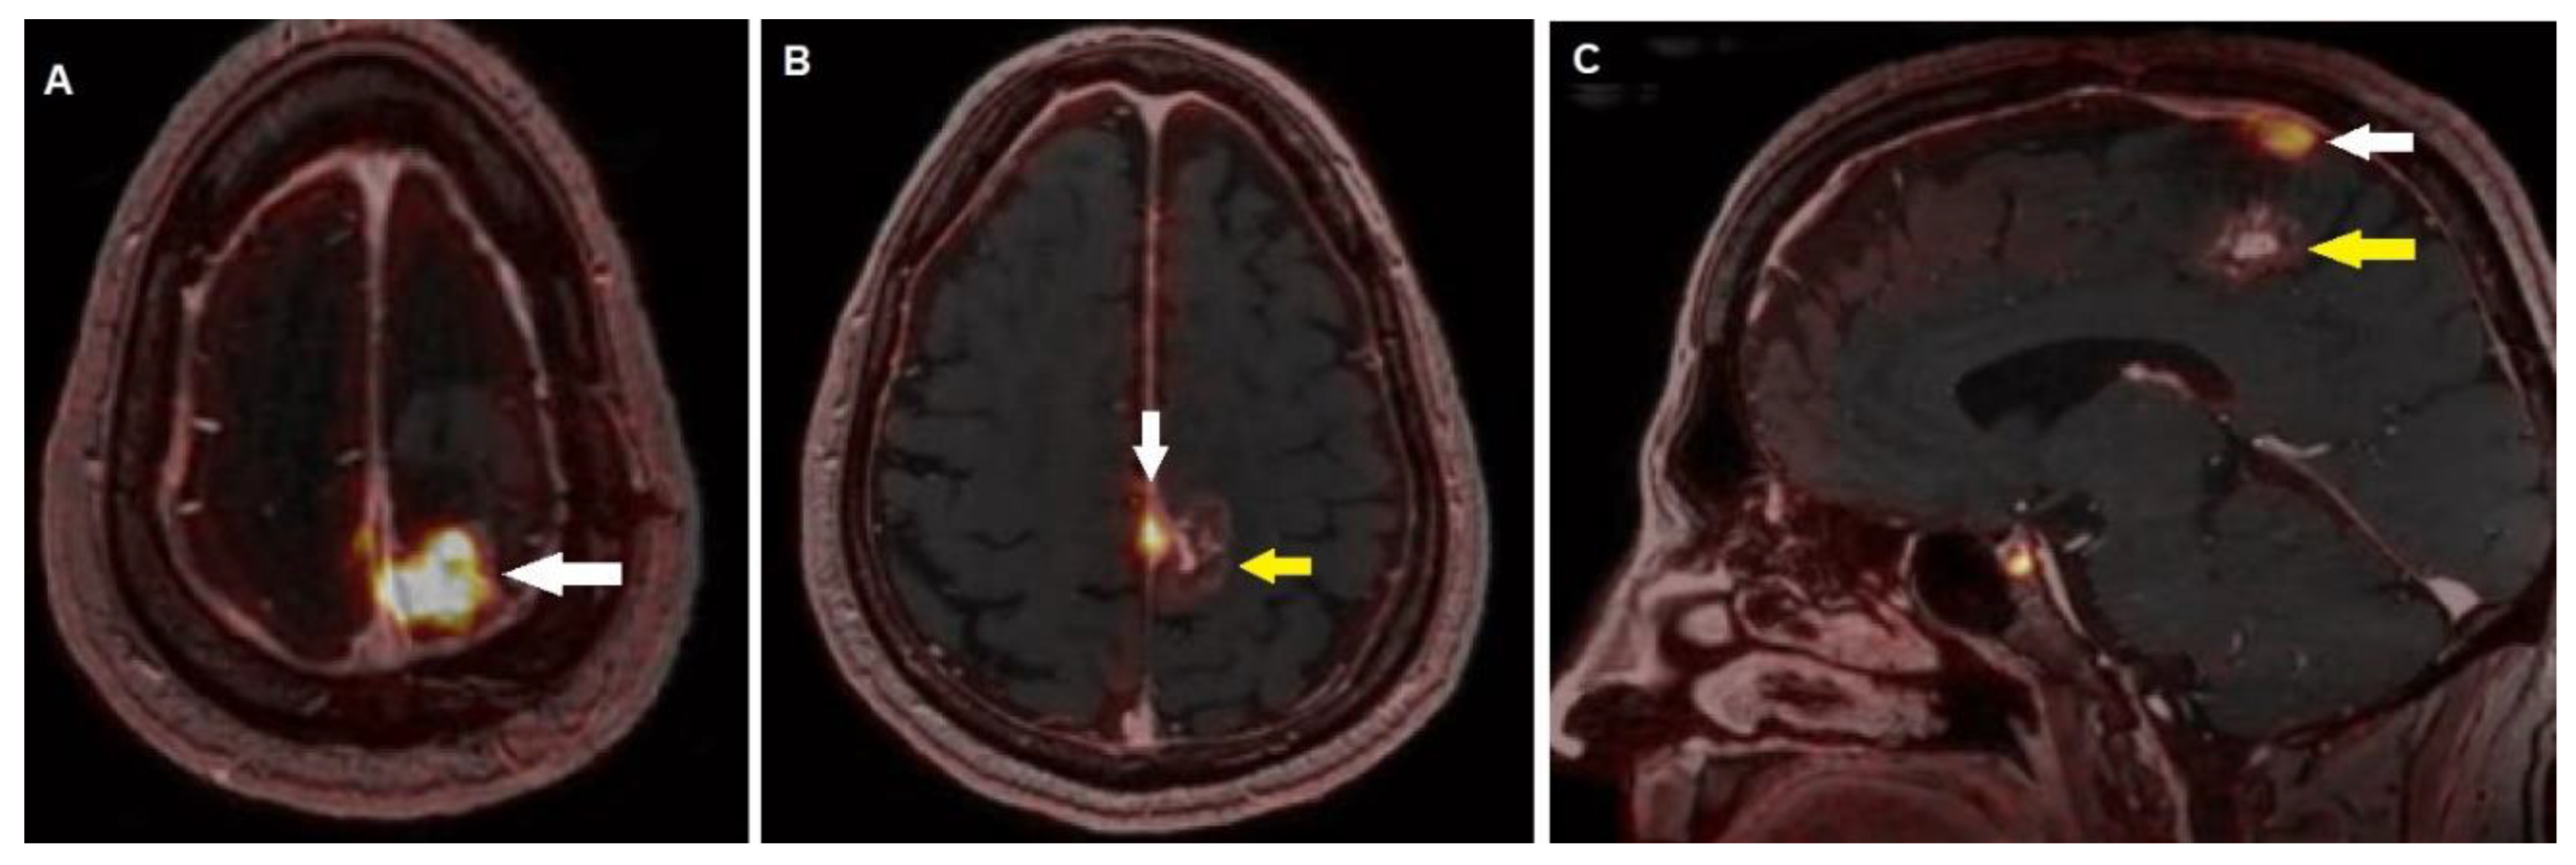

| Ivanidze et al. [30] | 2019 | USA | R (CS) | 17 | 49 | Useful of PET for pretreatment assessment, detection of recurrence, identification of additional lesions with respect to MRI | 68Ga-DOTATATE 185 MBq | PET/MRI (Biograph-mMR, Siemens) or (SIGNATM, GE Healthcare,) | Histology or follow-up | PET/MRI was useful to detect meningiomas, also revealing additional focuses with respect to conventional MRI. Furthermore, PET helped differentiating between post treatment change and tumor recurrence. |